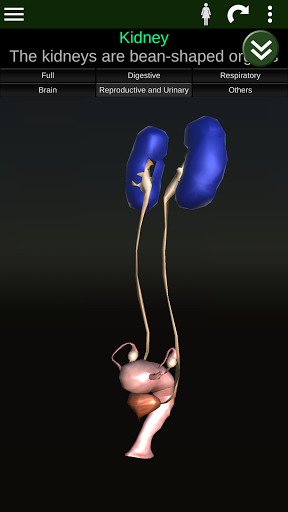

Menampilkan model anatomi 3D dari organ utama tubuh manusia dan penjelasannya masing-masing.

* Sistem reproduksi, yang meliputi organ reproduksi pria dan wanita.

* Mudah diakses dan dinavigasi (zoom, rotasi 3D).

* Deskripsi masing-masing organ.